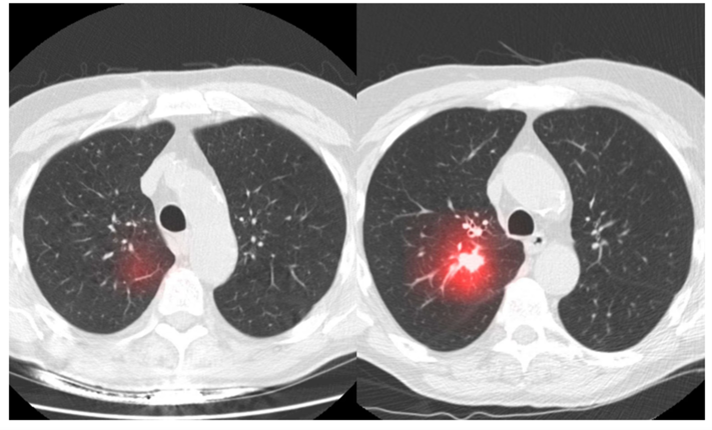

Starting with cancer prevention and early diagnosis, AI can be used for the analysis of clinical imaging to further help in the detection of the tumor (Figure 2). Other information gleaned from AI can be informative disease projection – estimating how the disease will progress – and the predicted efficacy of therapy. For an example of how AI can improve current medical practices, consider this: early detection of various cancer through conventional screening has various limitations. However, AI can be used for tumor screening by creating prediction models for each patient and identifying potential biomarkers (or alterations in cells or genes) that increase the risk of cancer. To illustrate another scenario, researchers at the National Cancer Institute (NCI) built algorithms to identify pre-cancerous cervical cells that need to be treated or removed. This algorithm, in some cases, is considered more effective and accurate than manually checking the cervix. AI algorithms were also able to predict the risk of patients developing breast cancer by analyzing and interpreting the patient’s mammogram.